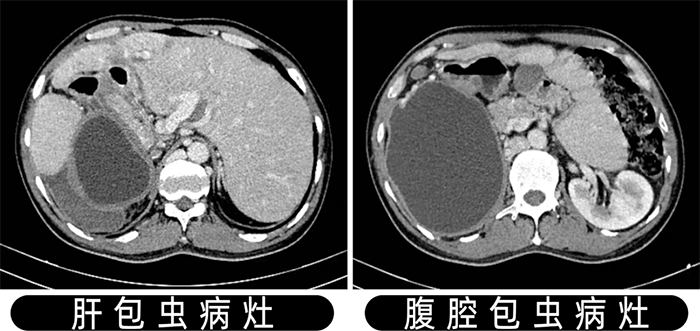

患者是一名中年男性,因“反復(fù)腹痛1月”住院于肝膽外科,經(jīng)腹部CT、彩超檢查提示:肝臟多發(fā)包蟲病灶及腹腔巨大包蟲病灶。

本次手術(shù),楊闖醫(yī)療團(tuán)隊借助數(shù)字化三維成像技術(shù),充分展示了肝臟包蟲病灶、腹腔包蟲病灶與重要組織器官的關(guān)系,成功精準(zhǔn)實施肝臟及腹腔包蟲病手術(shù),這標(biāo)志著我院肝膽外科對肝包蟲病的治療跨上新臺階。